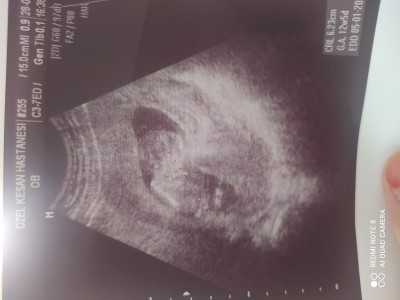

Linçlemeyin ne olur ilk gebeliğim yeni geldim doktordan ama hiç ilgilenmedi sizce ne cinsiyeti anlayan var mı :) şimdiden teşekkür ederim:))

Gebelik haftası 12+3

Erkeğe benziyor canım ensesinde çıkıntı var, Allah hayırlısını nasip etsin sen şartlama kendini daha yeniymiş